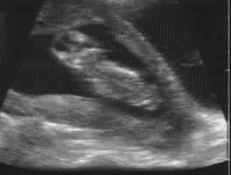

第1张图:上蹿下跳

在妈妈还没明显觉察到胎动时,宝宝在子宫里其实过得非常惬意。子宫对他来说空间足够,他会在里面“上蹿下跳”,甚至在做B超时,因为动得太厉害,有时连B超都难以捕捉清晰的数据。

所以妈妈去做B超前,可以准备一些食物,如果宝宝不配合,医生可能会让妈妈走动一下,等宝宝安静或转过身时再查看。